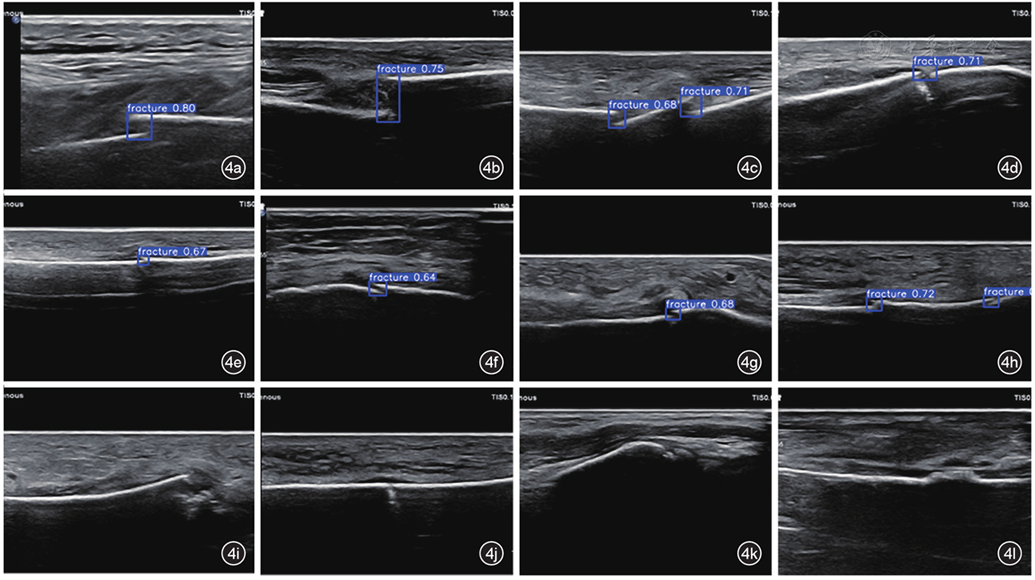

YOLO 11模型的预测框可准确检出断端,并且可以识别断端分离<3 mm的微骨折。然而,对不典型骨折断端(碎片样断端、骨皮质无分离、微小骨碎片、骨皮质局部隆起)存在漏检(图4)。

图4 基于YOLO 11的骨折断端超声检测模型对典型和非典型骨折的超声检测图像。图a~d为模型对典型骨折断端的超声检测图像,检测框精准检出骨折断端;图e~h为模型检出微骨折(断端分离<3 mm)的超声图像;图i~l分别为模型漏诊碎片样断端、骨皮质无明显分离、微小骨碎片及骨皮质局部隆起4种不典型骨折断端的超声图像